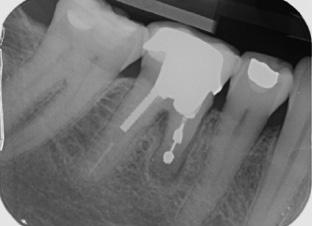

Marketing and branding yourself using social media platforms is essential as a selfemployed individual. Breaking that fear and anxiety of showcasing and promoting your before-and-after work, and highlighting patient testimonials on social media is not only important to demonstrate your skillset as a young dentist but also to boost your reputation and recognition for welcoming new patients. Having been fortunately selected as a finalist for multiple awards in the past including this year’s Dental Awards, it has not only boosted my esteem and confidence as a young dentist, but has encouraged me to keep steering this journey forward for the benefit of my patients’ healthcare and my own ability to provide excellent dentistry. Plus, receiving a shiny plaque to put on the wall for patients to see provides a confidence boost for them, as well as myself.

I personally use Instagram for my content. I was always hesitant to post images of my work in fear of being judged by other dentists, but eventually overcame this and told myself to have confidence in the quality of my work and just do it. That mindset has worked in my favour since. Sharing before-and-after cases (with patient consent), posting educational videos about common procedures, and fun moments behind the scenes to make your practice feel welcoming speaks for itself. Be sure to engage with your audience by answering questions, responding to comments and showing that you care.